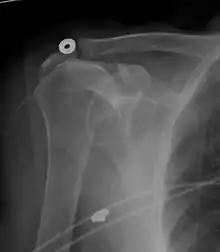

MRI

Magnetic resonance imaging (MRI) and ultrasound[46] are comparable in efficacy and helpful in diagnosis, although both have a false positive rate of 15–20%.[47] MRI can reliably detect most full-thickness tears, although very small pinpoint tears may be missed. In such situations, an MRI combined with an injection of contrast material, an MR-arthrogram, may help to confirm the diagnosis. It should be realized that a normal MRI cannot fully rule out a small tear (a false negative) while partial-thickness tears are not as reliably detected.[48] While MRI is sensitive in identifying tendon degeneration (tendinopathy), it may not reliably distinguish between a degenerative tendon and a partially torn tendon. Again, magnetic resonance arthrography can improve the differentiation.[48] An overall sensitivity of 91% (9% false negative rate) has been reported, indicating that magnetic resonance arthrography is reliable in the detection of partial-thickness rotator cuff tears.[48] However, its routine use is not advised, since it involves entering the joint with a needle, with the potential risk of infection. Consequently, the test is reserved for cases in which the diagnosis remains unclear.

Diagnostic modalities, dependent on circumstances, include X-ray, MRI, MR arthrography, double-contrast arthrography, and ultrasound. Although MR arthrography is currently considered the gold standard, ultrasound may be most cost-effective.[34] Usually, a tear will be undetected by X-ray, although bone spurs, which can impinge upon the rotator cuff tendons, may be visible.[35] Such spurs suggest chronic severe rotator cuff disease. Double-contrast arthrography involves injecting contrast dye into the shoulder joint to detect leakage out of the injured rotator cuff,[36] and its value is influenced by the experience of the operator. The most common diagnostic tool is magnetic resonance imaging (MRI), which can sometimes indicate the size of the tear, as well as its location within the tendon. Furthermore, MRI enables the detection or exclusion of complete rotator cuff tears with reasonable accuracy and is also suitable for diagnosing other pathologies of the shoulder joint.[37]